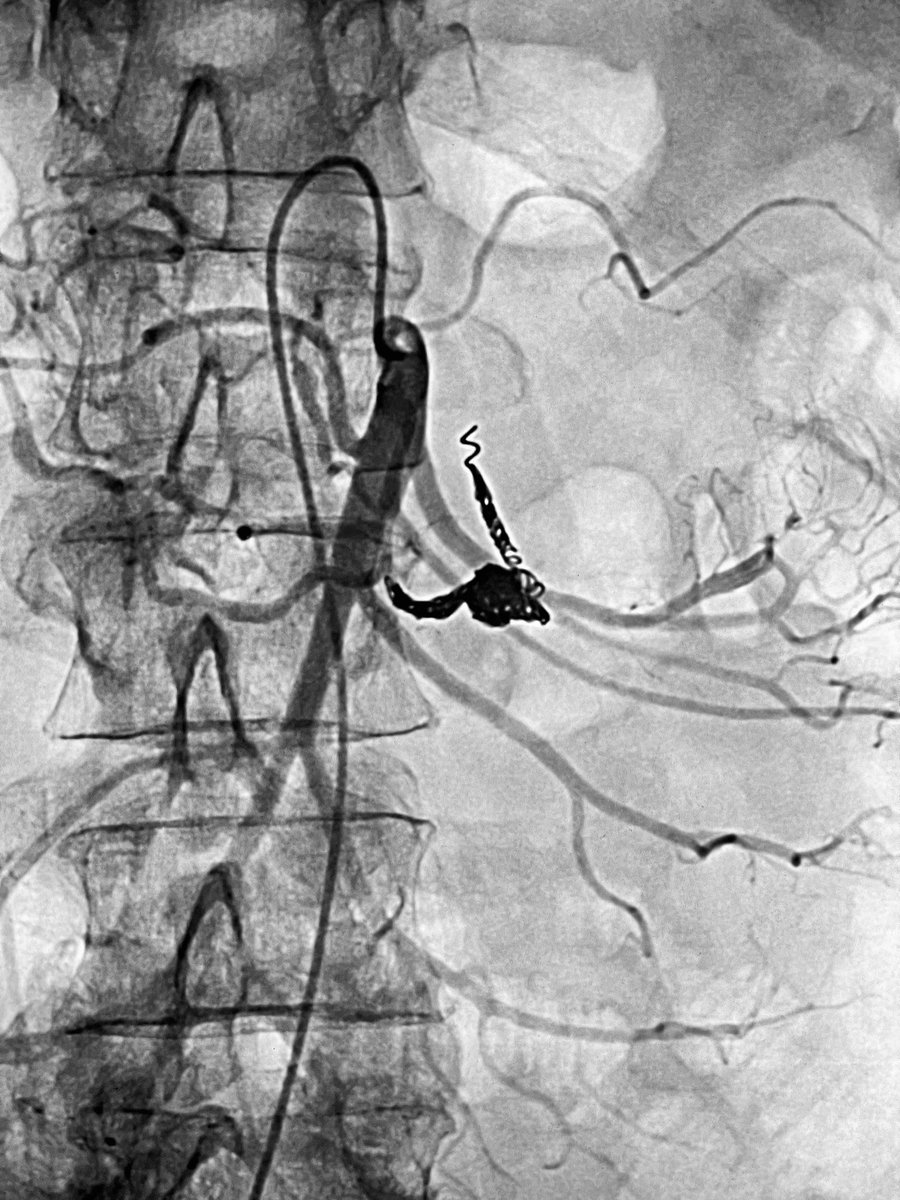

Live @MountSinaiIR 25mm superior mesenteric artery aneurysm in a 34 yr old vEDS pt (existing coils from a previous ruptured splenic artery aneurysm) what to do? How to manage?

@DrShannonThomas @SIRRFS @SIR_ECS Correct! Coiled the aneurysm and the inflow/outflow with Penumbra Ruby, POD and Packing coils. @VA_Int_Oncology @VenuVadlamudiMD @PenVascular